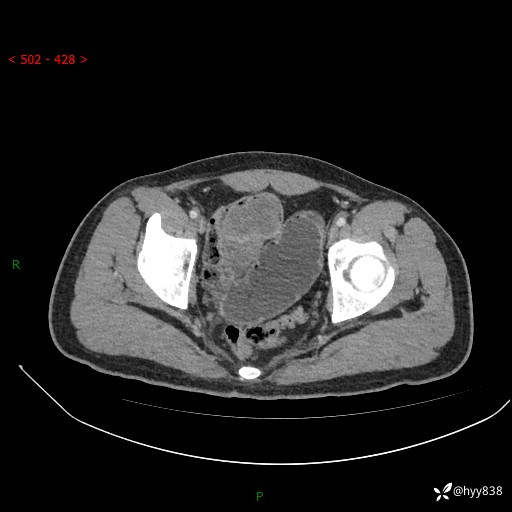

年轻男性,腹痛5月余。除了肠梗阻,你还能看到什么---结果公布~

现病史:患者于5月前无明显诱因开始出现腹痛,上明显,为间断性胀痛不适,无畏寒发热,无心慌气促等特殊不适,遂来我院。我院门诊遂以“腹痛原因待查”收入我科。 起病以来,患者精神、饮食、睡眠欠佳,大小便正常。体力体重无明显变化。

腹部CT增强扫描(动脉期+静脉期)